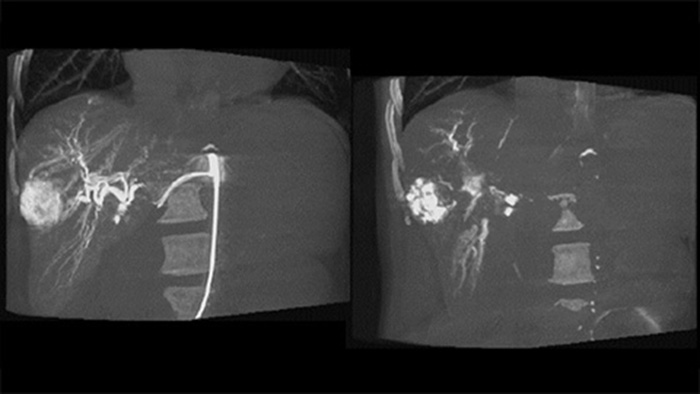

Una adquisición 3D posterior a la embolización le permite visualizar el depósito objetivo del material embólico, como Liopidol o perlas radiopacas, en el tumor5.

Dual View permite la visualización simultánea de la imagen 3D de fase arterial previa a la embolización y la imagen posterior a la embolización para evaluar el criterio de valoración del tratamiento.